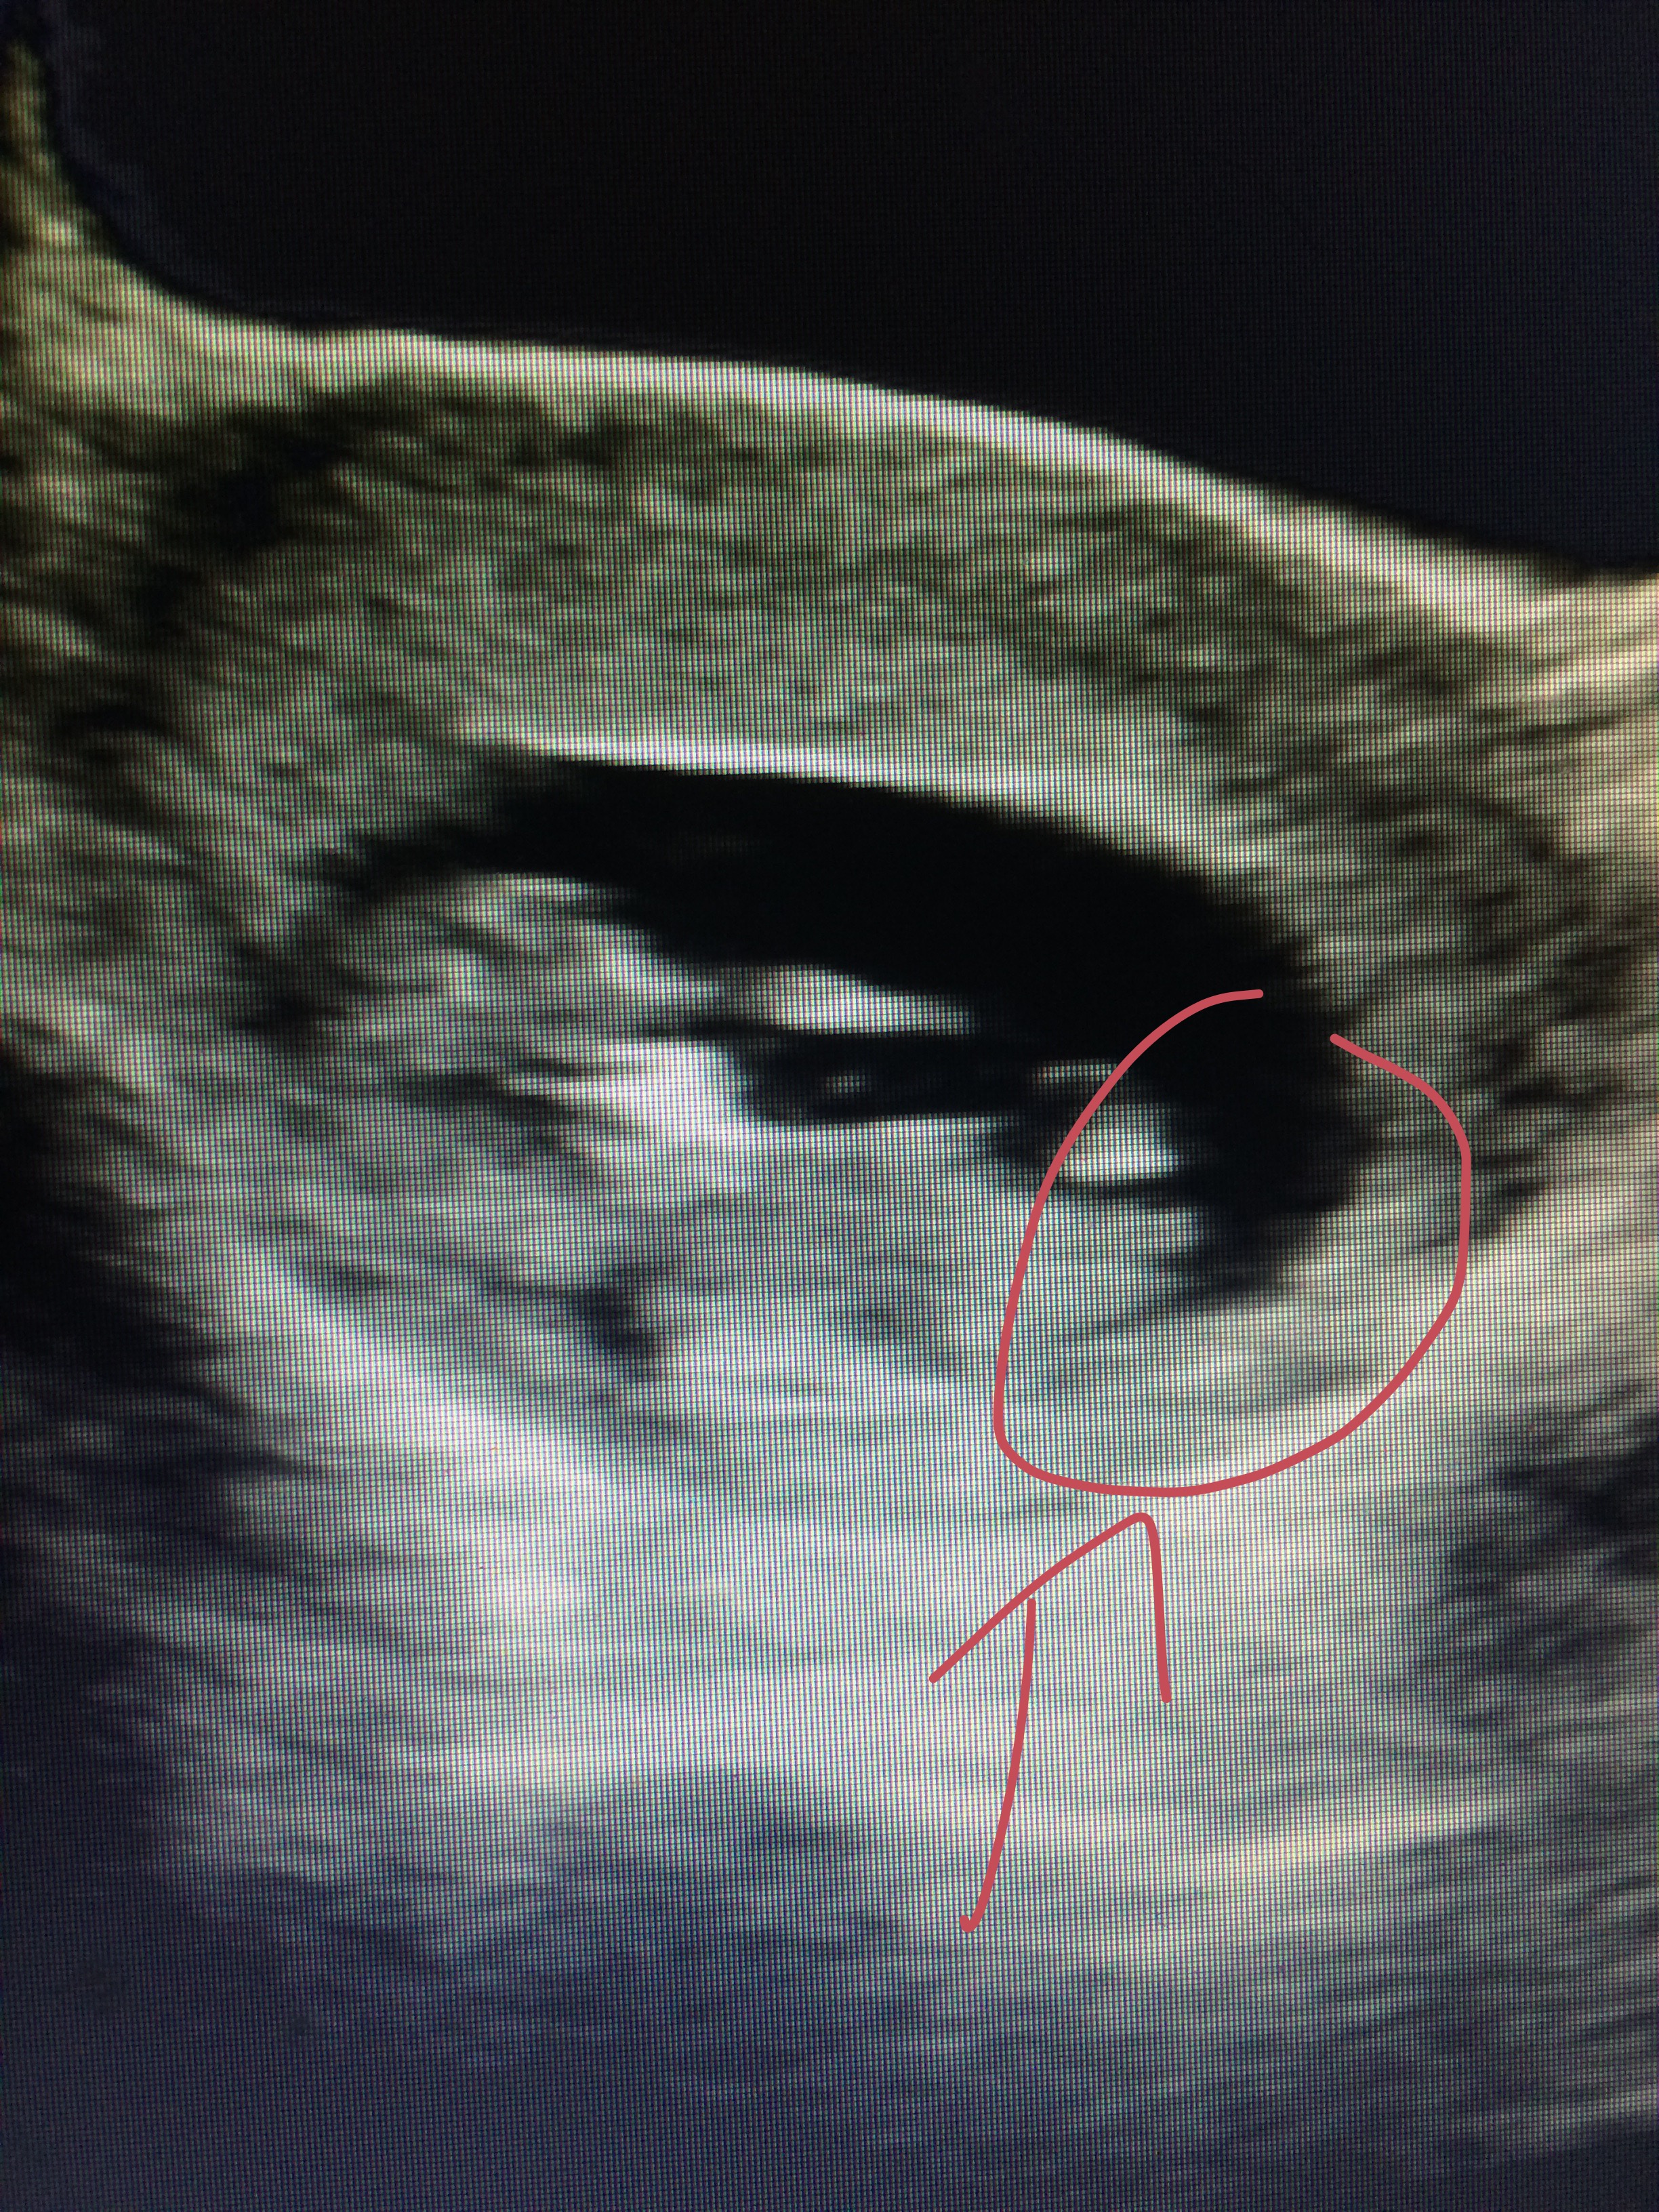

I'm not sure if the part I circled is the nub or not?!? If it is is it a boy or girl nub?!?Attachment 27910

Probably a girly nub

Looks girly but if you are only just 12 weeks then it's too early to really give definitive answer

It looks girly but its a little early and the baby looks rotated a bit :). Good luck!